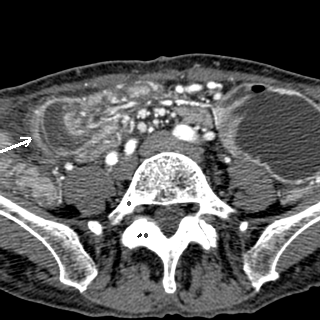

- Occlusion des hernies inguinales etranglees :

Aspect radiologique de occlusion des hernies etranglee est

image de l'obtacle se situe a la region inguino-scrotale (

hernie crurale ou hernie au dessus de arcade crurale ) , au

trous obturateurs ou a la ligne blanche + Image de

distention de l'intestin en amont de l'obtacle

| Hernie inguinale etranglee : Image TDM en

coupe axiale a travers L5 |

| Hernie inguinale etrangle : Image

d'engage du grele dans fossette inguinale

moyenne + image de distension de l'intestin au

dessus de l'obstacle ( fleche rouge ) . |

La TDM est tres

l'interet de presiser facilement le type de hernie :

hernie inguinale direct etrangle avec image de grele

en de dans des vaisseaux epigastriques .La TDM peut

differentiele avec les autres masses de la region

scrotale . |